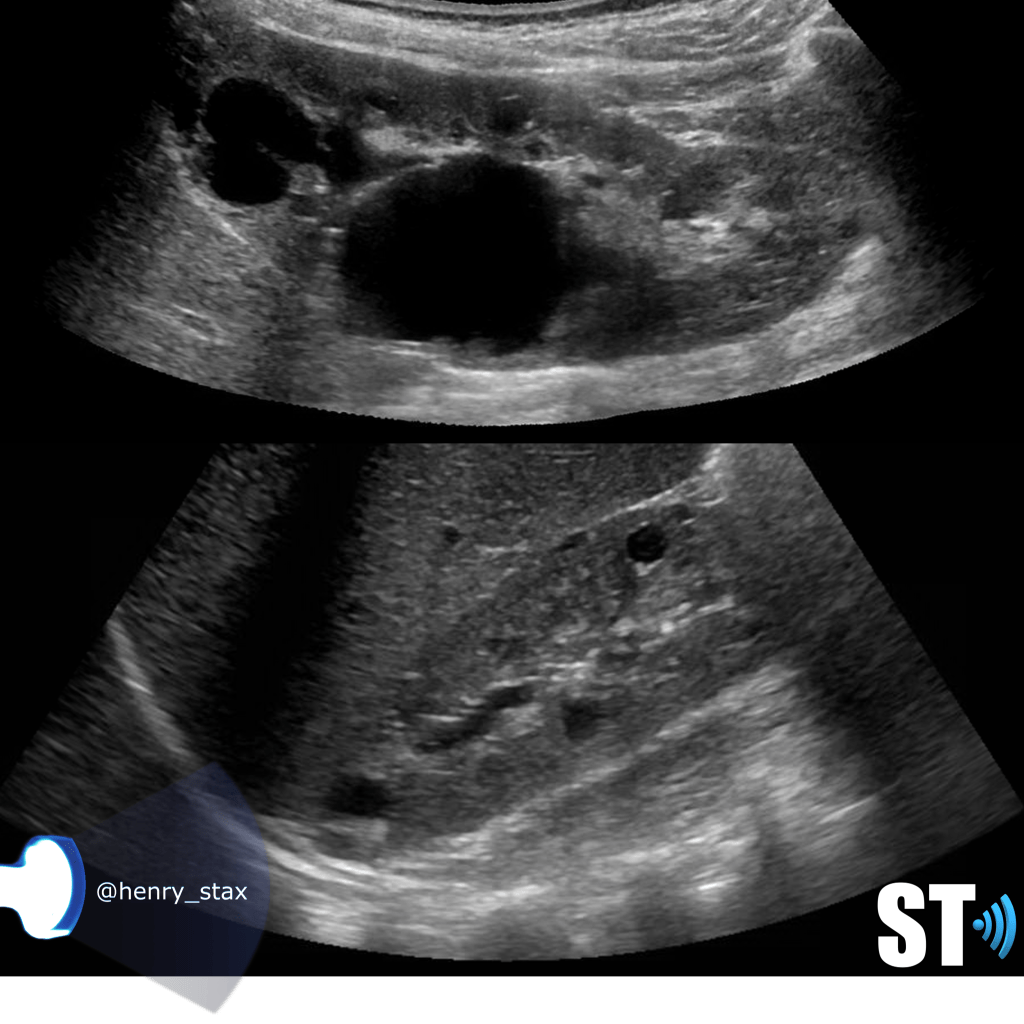

Acute pyelonephritis

Bacterial inflammatory disease of the kidney is commonly cause Eschericia coli. Most infections begin as UTI that ascends to the upper genitourinary system. the infection spreads from the renal pyramids into the renal cortex. The infection may be focal or diffuse. This condition usually presents with chills, fever, flank pain and laboratory findings of urinary infection.

Ultrasound may show an enlarged kidney with edema and increased echogenicity. You may also see a focal triangular area of altered echogenicity that displays reduced perfusion with color Doppler and power Doppler. If left untreated or inadequately treated that area can turn into an abscess.

An abscess will be well formed and distinct from the remainder of the renal parenchyma, it will be heterogeneous, complex appearance with mixed echoic and anechoic portions and no color doppler signal internally..

Once an abscess has formed drainage under ultrasound guidance can be performed. On subsequent imaging you notice some cortical thinning where the abscess was representing scarring.